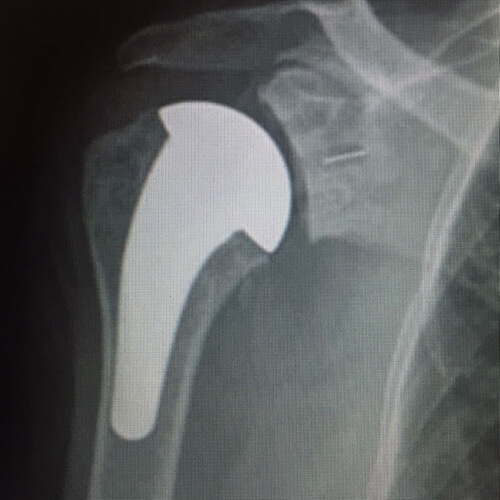

L’EPAULE

Arthroplastie

Remplacement prothétique des surfaces de l'articulation, prothèse totale d'épaule. Prothèse anatomique ou inversée.

Concernant les pathologies de l’épaule : une radiographie associée à une échographie sont déjà fort intéressantes. Pour un bilan plus précis un arthoscanner est souvent nécessaire, notamment lorsque l'on envisage une réparation tendineuse.